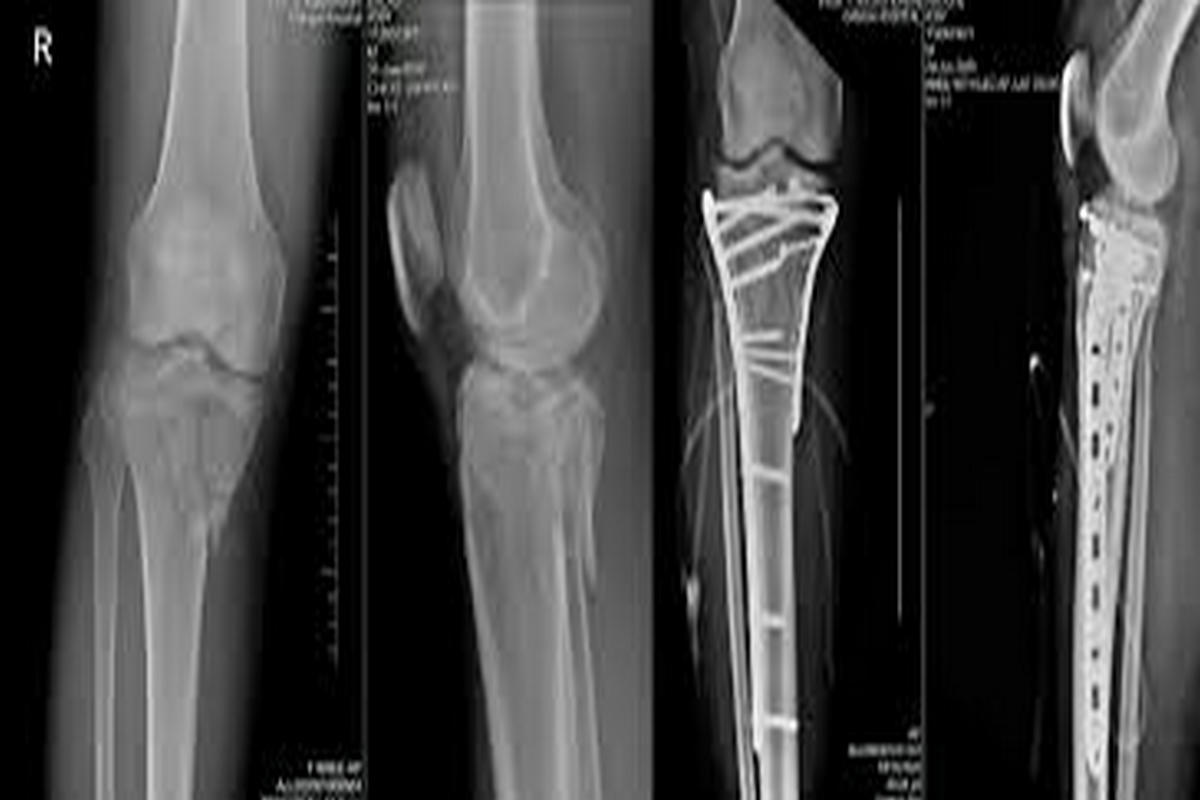

Διαϋπερκονδύλια κατάγματα μηριαίου

Τα διαϋπερκονδύλια κατάγματα εντοπίζονται στο κατώτερο άκρο του μηριαίου οστού, ακριβώς πάνω από την άρθρωση του γόνατος.

Συνήθως προκαλούνται από τραυματισμούς υψηλής ενέργειας, όπως τροχαία ατυχήματα ή πτώσεις από ύψος. Σε ηλικιωμένους ασθενείς με οστεοπόρωση, μπορεί να εμφανιστούν ακόμη και μετά από χαμηλής ενέργειας κάκωση.

Οι ασθενείς παρουσιάζουν έντονο πόνο, οίδημα, αδυναμία στήριξης του σκέλους και συχνά εμφανή παραμόρφωση. Η διάγνωση γίνεται με ακτινογραφίες, ενώ η αξονική τομογραφία είναι απαραίτητη για την ακριβή εκτίμηση της γραμμής και της πολυπλοκότητας του κατάγματος.

Η θεραπεία είναι κατά κανόνα χειρουργική και περιλαμβάνει οστεοσύνθεση με πλάκες και βίδες ή ενδομυελικούς ήλους, με στόχο την ανατομική ανάταξη και τη σταθερότητα. Συντηρητική αγωγή εφαρμόζεται σπάνια και μόνο σε ασθενείς που δεν μπορούν να υποβληθούν σε χειρουργείο.

Πιθανές επιπλοκές είναι η μη πώρωση, η δυσκαμψία του γόνατος και η ανάπτυξη μετατραυματικής αρθρίτιδας.